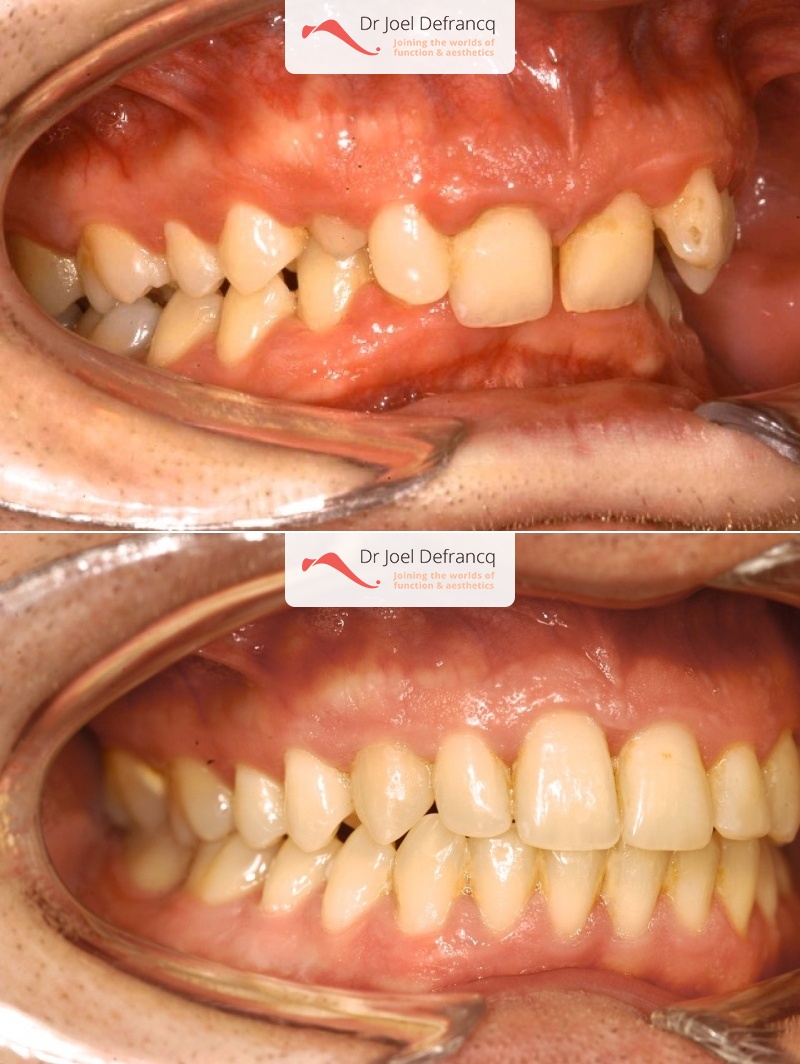

- Te kleine onderkaak (Overbeet)

- Klasse II divisie 2